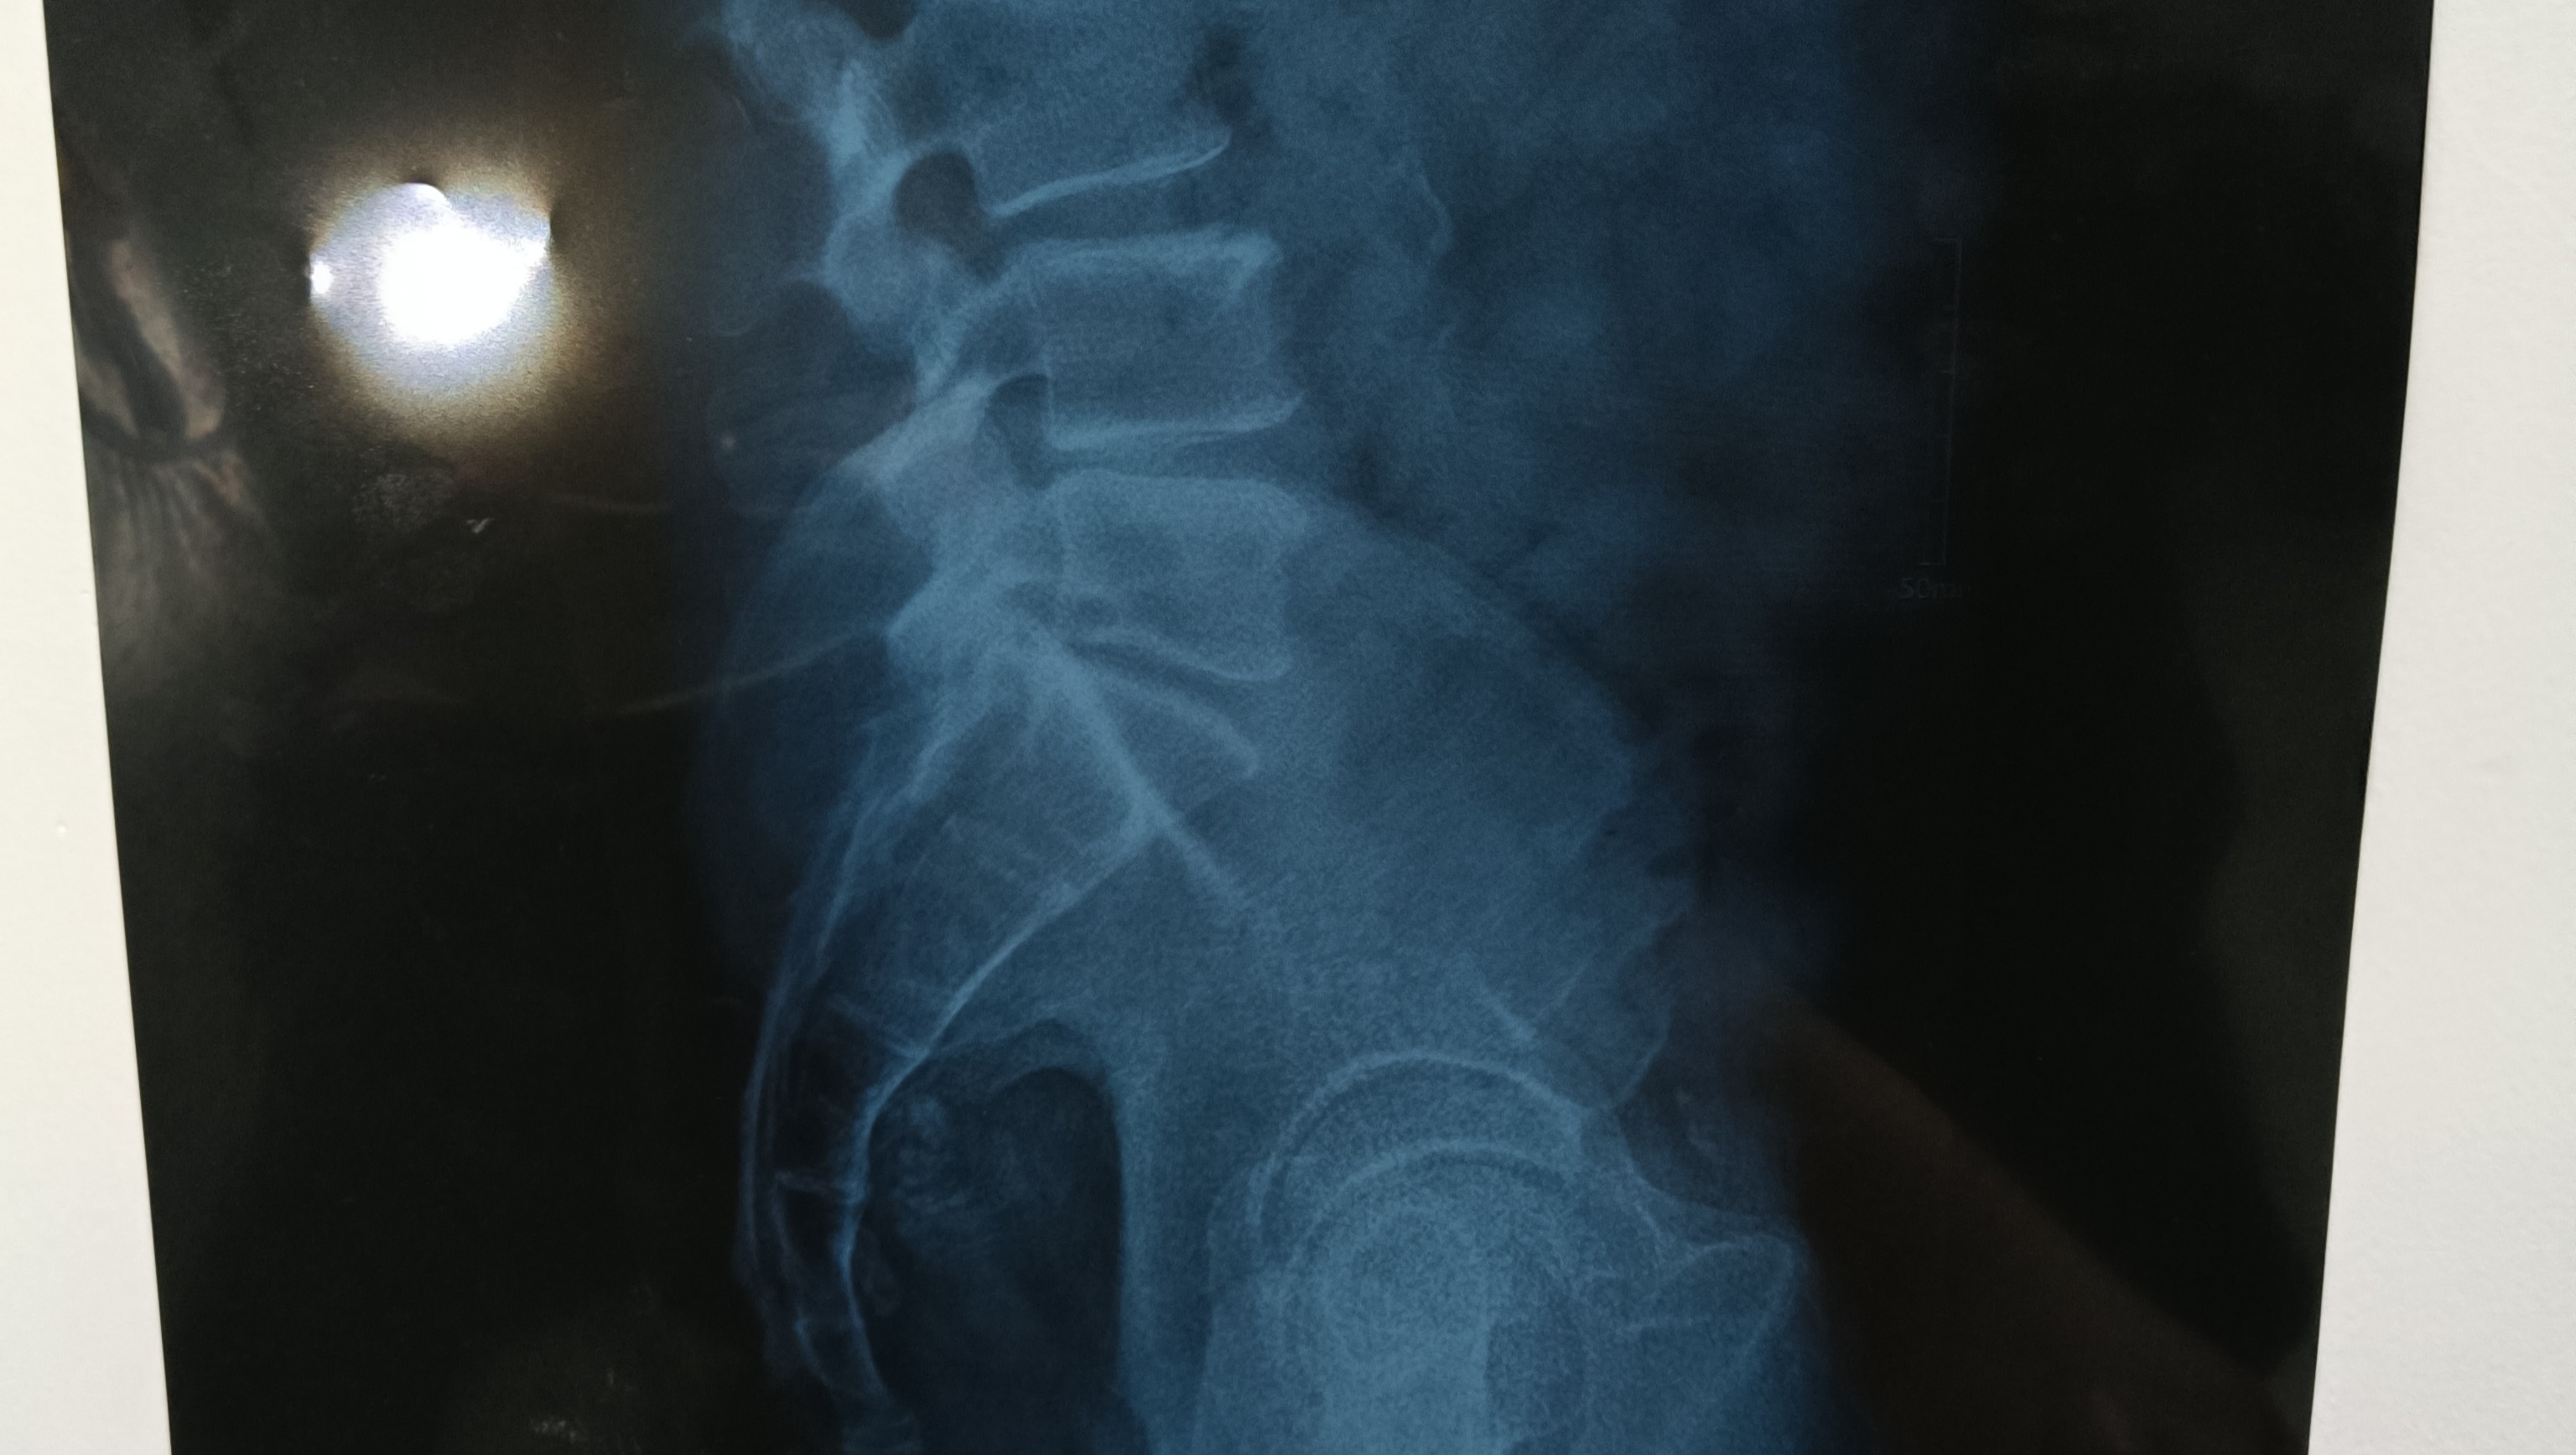

Hola me llamo Sarahi, recaudo fondos para mi papá que necesita una operación de columna urgente, tiene 62 años. No puede caminar hasta que se realice la operación y lamentablemente no tenemos los recursos económicos para poder operarlo, hemos intentado acudir a instancias de gobierno y nos nos dan una cita de consulta inicial hasta dentro de 8 meses y la operación se precisa con urgencia, porque corre el riesgo de perder sensibilidad en las piernas, así mismo podría ocasionar incontinencia. Y quiero que tenga una mejor calidad de vida, en la medida de lo posible. Gracias por tu ayuda ❤️